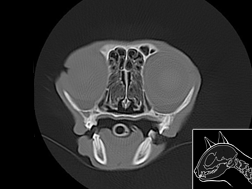

Ces atlas sont présentés par région : cérébrale, thoracique et abdominale. Deux techniques d’imagerie ont été utilisées : le scanner et l’IRM. Les atlas sont présentés en coupes transversales dans le sens cranio-caudal. Pour le scanner, deux fenêtrages ont été utilisés : tissu osseux et tissu mou. Pour l’IRM deux pondérations ont été utilisées : T1 et T2.

Atlas cérebral du chien SCTO

Scanner tissu osseux

>> 30 coupes

Atlas cérébral du chat SCTO

Scanner tissu osseux

>> 18 coupes